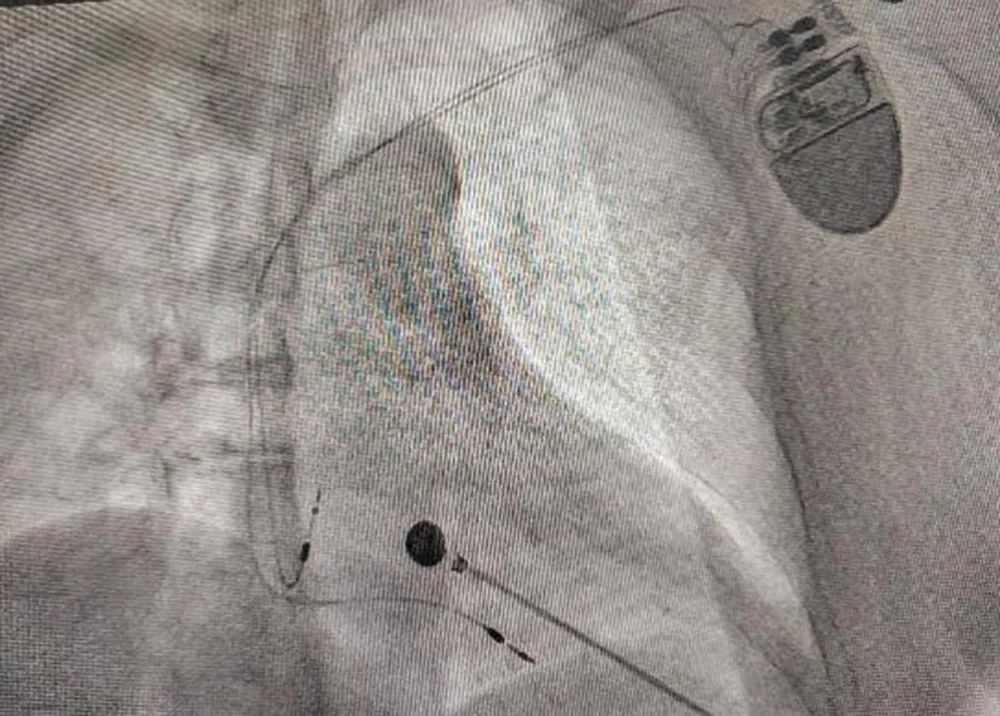

手术当天,患者行局部麻醉,全程处于清醒状态。历时1个多小时,在X线及多导电生理仪指导下,精确找到患者左束支起搏区域,将心室起搏电极头端通过室间隔右室侧旋转到室间隔左室侧左束支区域,起搏夺获左束支及其近端分支,心电图形成类似右束支阻滞的较窄QRS心电图。在实现良好的心室率起搏控制的同时又实现较大化的心室电机械同步。

术后影像